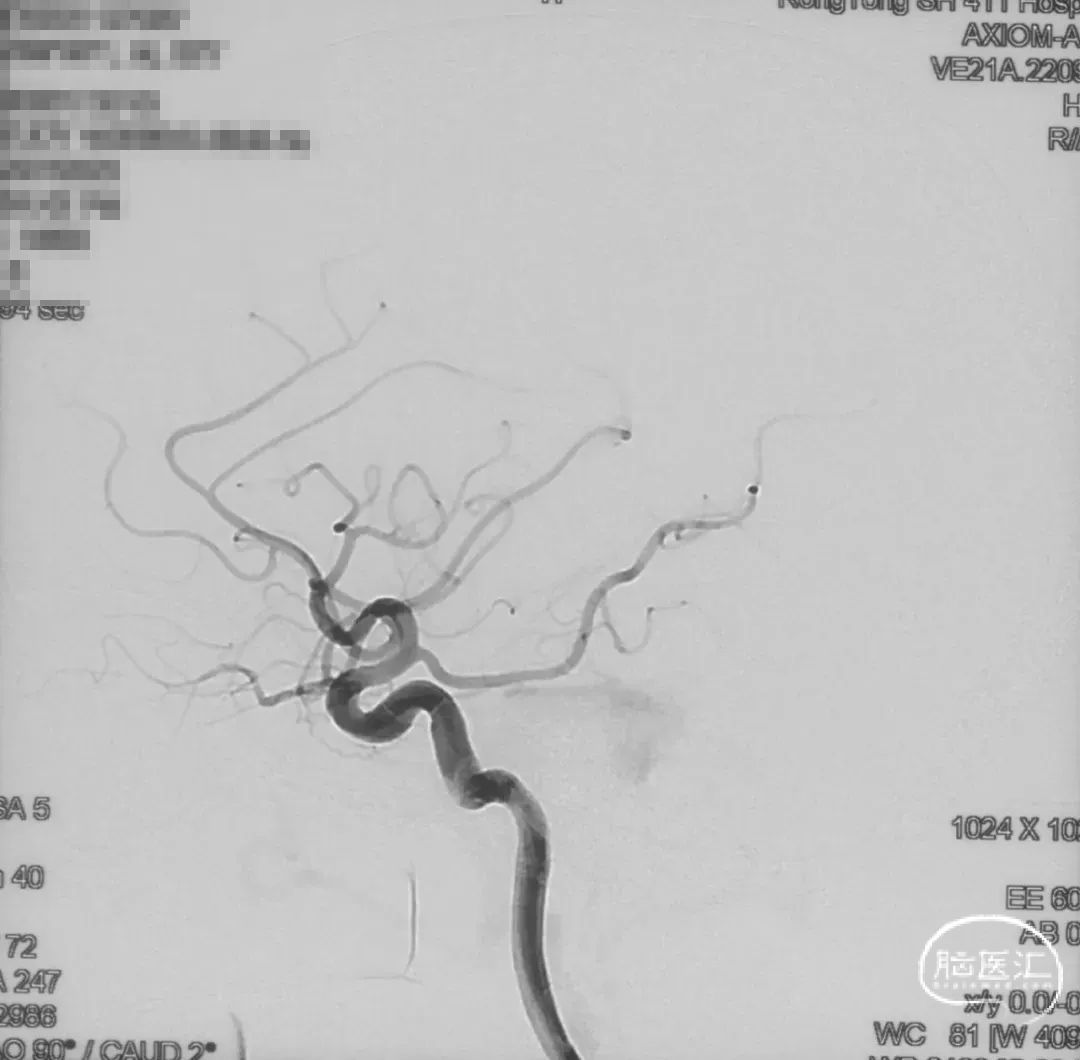

证实为TDAVF,为岩上窦型。R-ECA正侧位见右侧脑膜中动脉分支、枕动脉分支、颞浅动脉分支向瘘口供血,经幕上迂曲扩张的静脉、中脑周围静脉、基底静脉向深部静脉引流。

R-ICA正侧位见右侧脑膜垂体干向瘘口供血

L-ICA正侧位见左侧脑膜垂体干分支向瘘口供血

L-ECA正侧位未见向瘘口供血

L-VA、R-VA正侧位右侧小脑上动脉脑膜支向瘘口供血

选取工作角度,正侧位造影